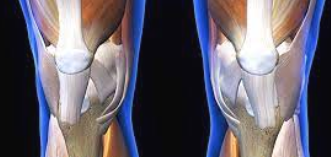

2단계: 중등도 연골 손상 증상

연골 손상이 중등도로 진행되면 증상이 더욱 뚜렷해집니다. 계단 오르내리기, 쪼그려 앉기, 장시간 걷기 등의 활동에서 명확한 통증이 나타납니다. 무릎 관절에서 소리가 자주 나며, 무릎을 완전히 구부리거나 펴는 것이 어려워집니다.

이 단계에서는 무릎 부종이 눈에 띄게 나타나며, 활동 후 무릎이 무겁고 뻣뻣한 느낌이 지속됩니다. 진통제를 복용해야 할 정도의 통증이 발생하며, 수면 중에도 무릎 때문에 잠을 깨는 경우가 생깁니다.